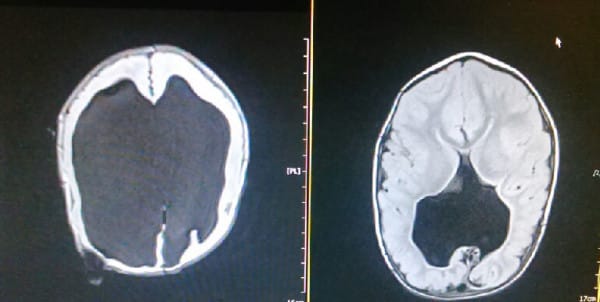

诺亚出生后,由于脑水肿的影响,98%的脑袋无法运作。但随着他慢慢成长,不可思议的事发生了。他的大脑逐渐长回来,让医生们都难以置信。

即使他需要比其他小孩花更多的时间成长,但现在4岁的他可以讲话,而且基本上拥有与同龄儿童相同的大脑。虽然诺亚仍然面临各种可怕并发症 (如脊柱裂) 的威胁,但他惊人的恢复能力震惊全球。BBC也有拍摄关于诺亚的纪录片,称这个令人难以置信的宝宝为无脑男孩。